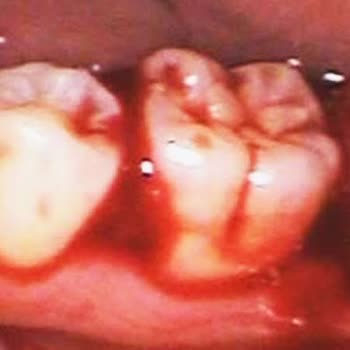

16 Şubat 2026 tarihinde İnegöl Ağız ve Diş Sağlığı Hastanesi’nde Dr. H**’e muayene oldum. Hamilelik düşündüğümü, bu nedenle ağzımda herhangi bir çürük ya da problemli diş varsa hepsini önceden yaptırmak istediğimi özellikle belirttim. Daha önce kanal tedavisi görmüş bir dişimde uzun zamandır çok şid...